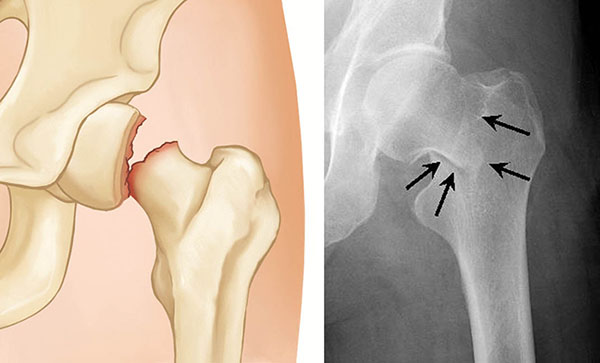

Geriatric hip fractures are fractures in the upper-third of the thigh bone (femur) and/or around the hip joint sustained by elderly adults as a result of a fall.

A health care provider can often diagnose a hip fracture based on symptoms and the abnormal position of the hip and leg. An X-ray usually will confirm the fracture and show where the fracture is.

If your X-ray doesn't show a fracture but you still have hip pain, your provider might order an MRI or bone scan to look for a hairline fracture.